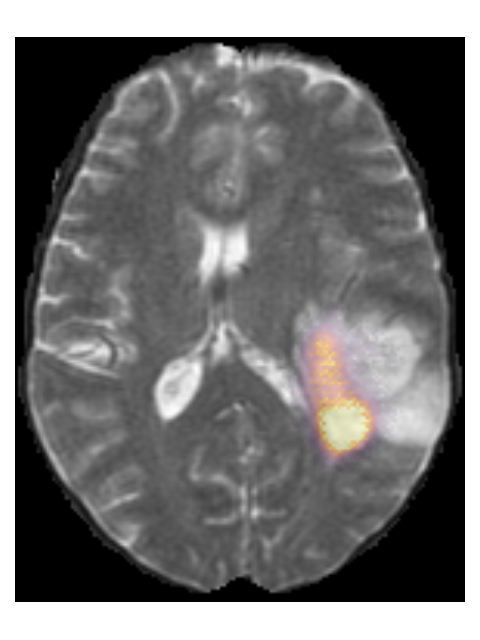

Finally, we considered two examples of scans that were incorrectly predicted by our method, see Figure 9. These two examples were chosen because our network assigned high prediction scores to the wrong classes for these cases. Figure 9(a) shows an example of a grade II, IDH mutated, 1p/19q co-deleted glioma that was predicted as grade IV, IDH wildtype by our method. Our method’s prediction was most likely caused by the hyperintensities in the post-contrast T1w scan being interpreted as contrast enhancement. Since these hyperintensities are also present in the pre-contrast T1w scan they are most likely calcifications, and the radiological appearance of this tumor is indicative of an oligodendroglioma. Figure 9(b) shows an example of a grade IV, IDH wildtype glioma that was predicted as a grade III, IDH mutated glioma by our method.